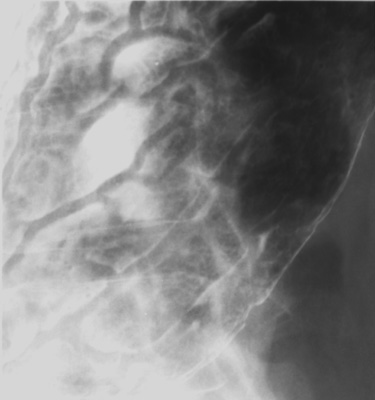

- Gastric body, inferior portion (patient supine, AP)